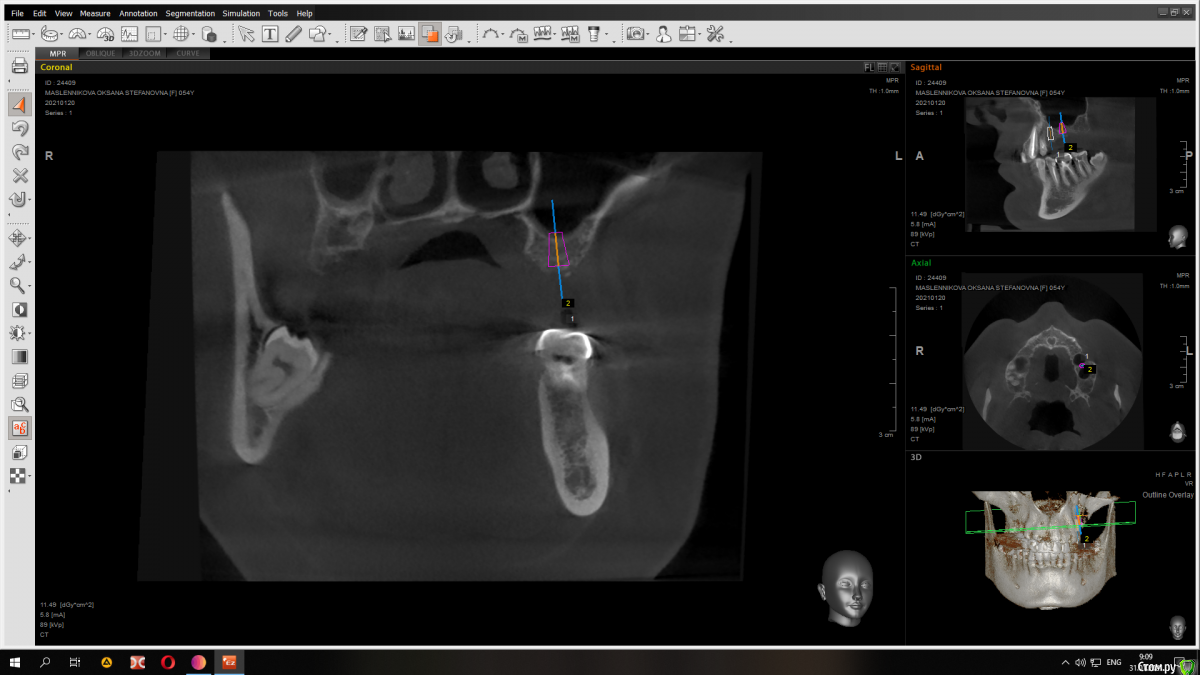

Raystom Опубликовано 31 января, 2021 Автор Поделиться Опубликовано 31 января, 2021 Вот 7мм Ссылка на комментарий

red_butler Опубликовано 31 января, 2021 Поделиться Опубликовано 31 января, 2021 Имхо замеры сделаны не правильно, но не вижу проблем. Если нет остеотомов, то закрытый синуслифт можно выполнить имплантом 1 Ссылка на комментарий

Raystom Опубликовано 31 января, 2021 Автор Поделиться Опубликовано 31 января, 2021 Имхо замеры сделаны не правильно, но не вижу проблем. Если нет остеотомов, то закрытый синуслифт можно выполнить имплантом в чем ошибка в замерах? Ссылка на комментарий

red_butler Опубликовано 31 января, 2021 Поделиться Опубликовано 31 января, 2021 в чем ошибка в замерах?замеры используя шаблон импланта Ссылка на комментарий